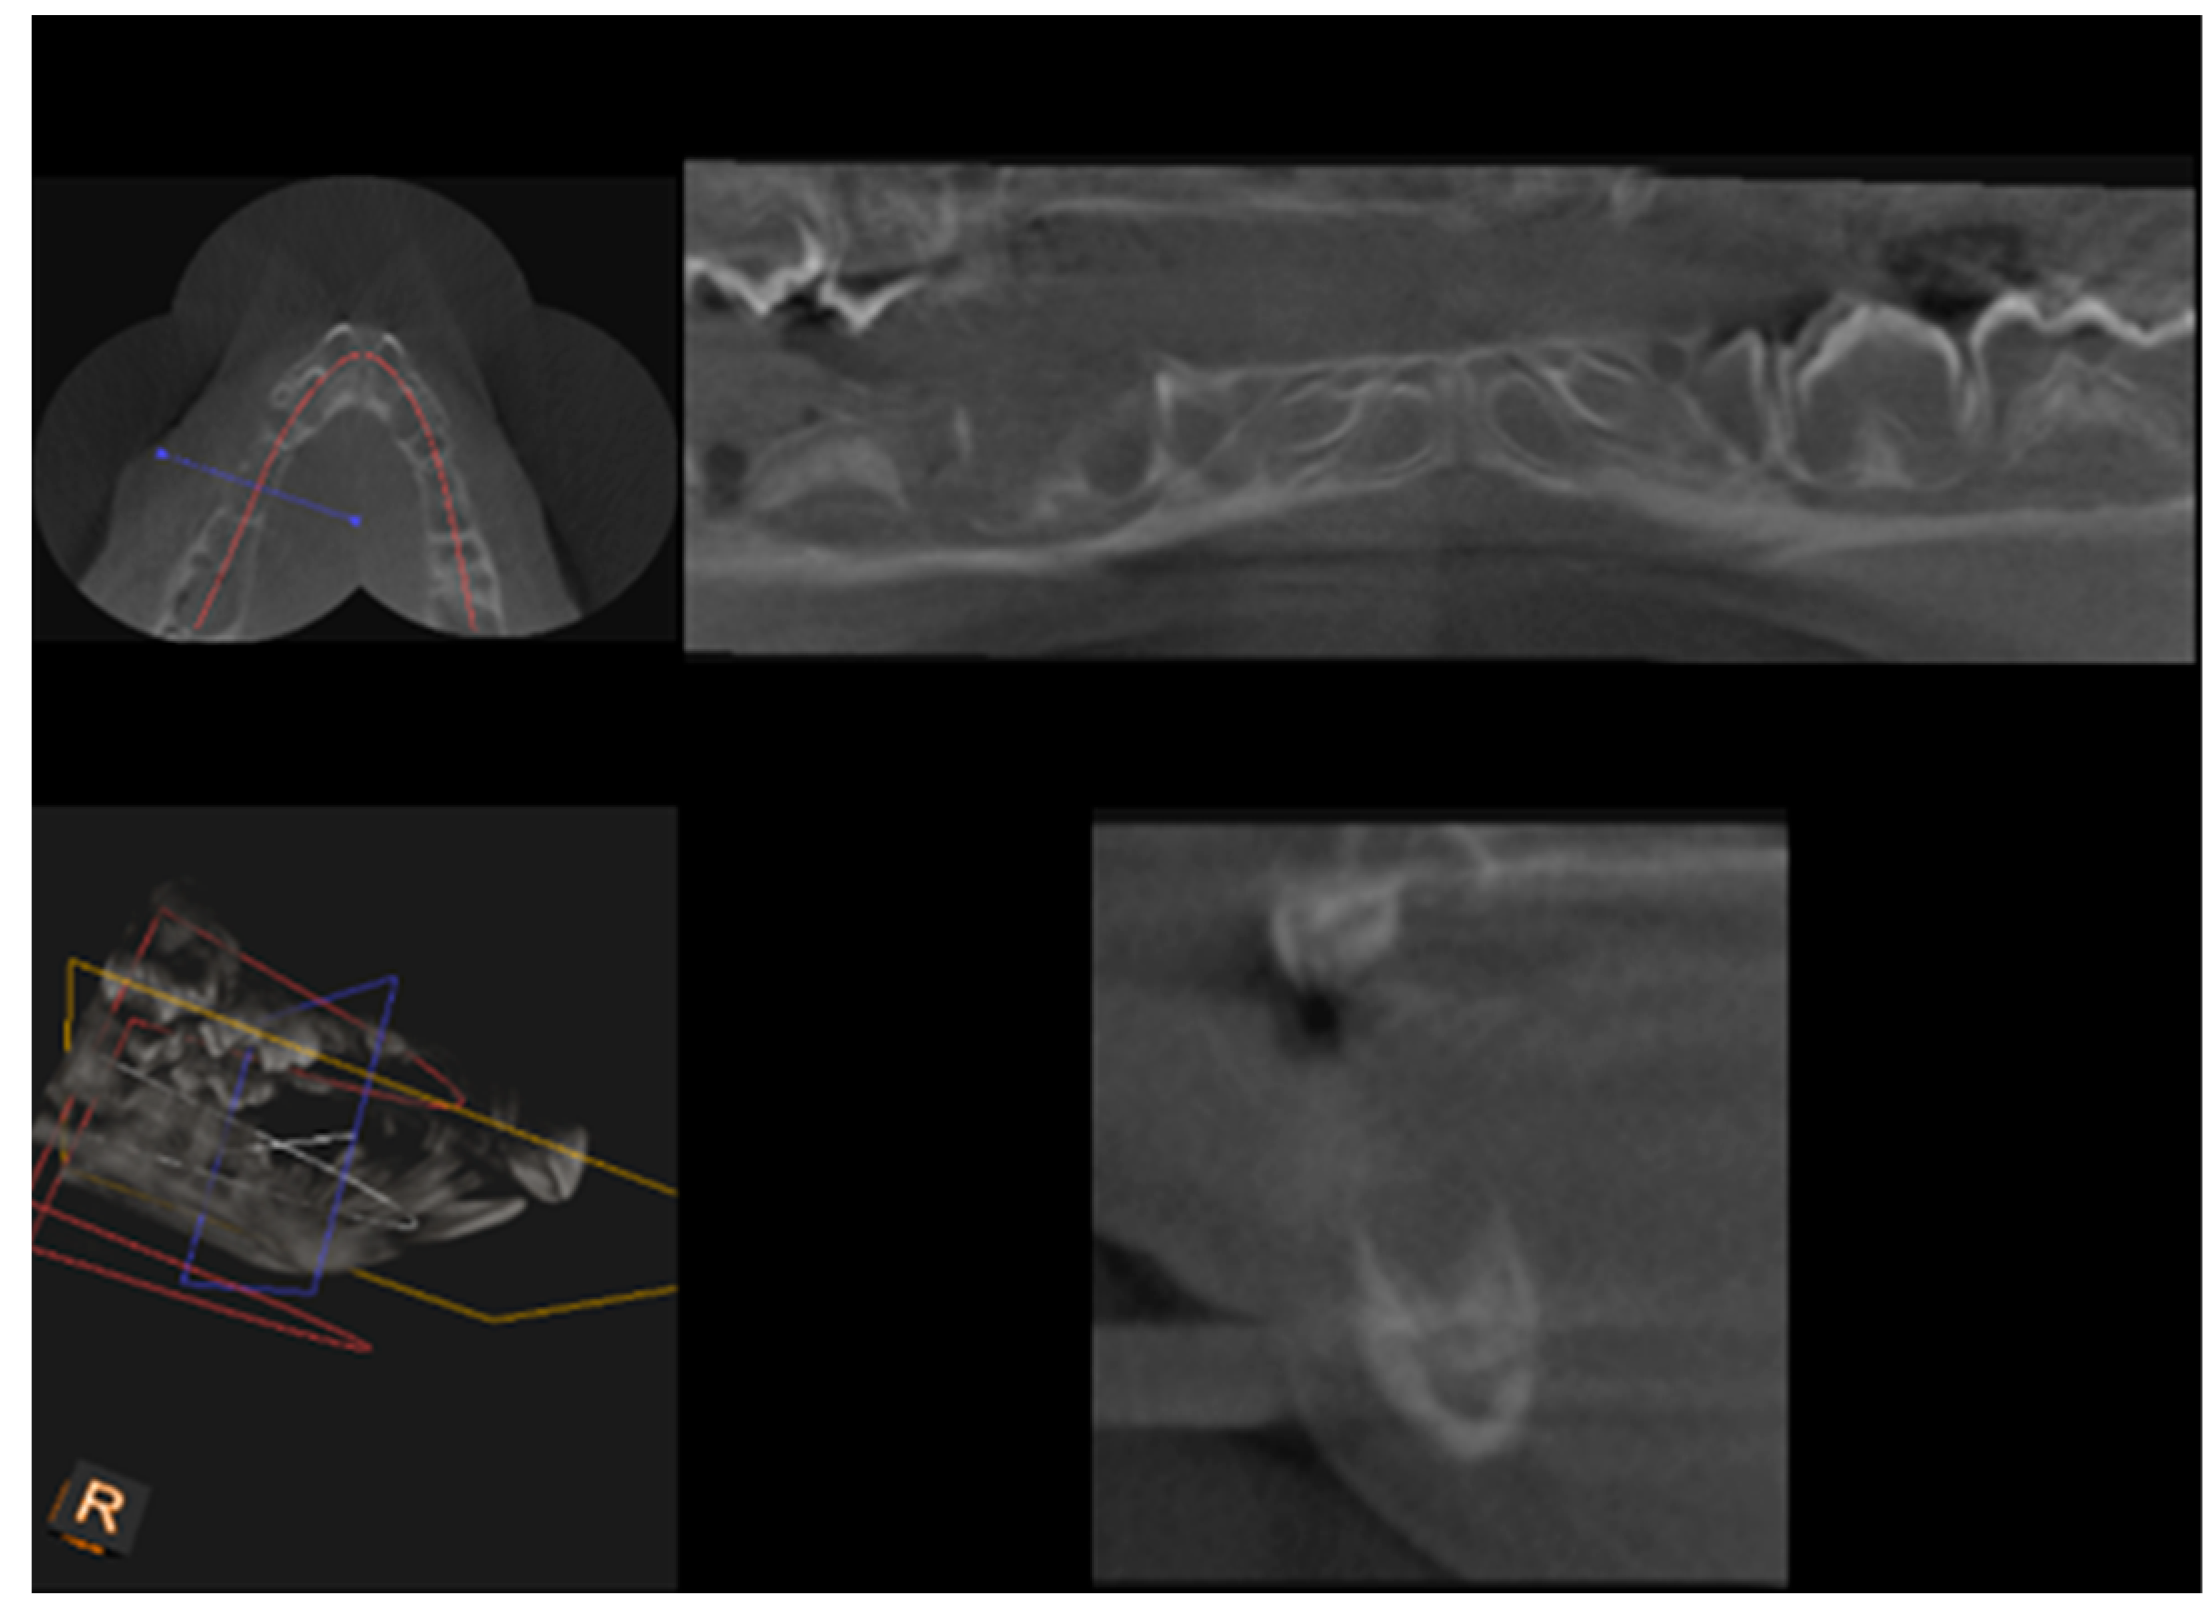

CBCT examination, with a Kodak 3000C 3D system (Kodak Dental Systems, Atlanta, GA, USA), together with Dental Imaging Software ver. 6.12.32 (Kodak Dental Systems, Atlanta, GA, USA), was performed before and immediately after germectomy and then again on the extracted jaws of the piglets after euthanasia with a voxel size of 160 μm, a 0.16 mm space between slices and a field of view of 13 × 10 cm, 90 kV and 4 mA. CT sections were used to assess the width and height of the bone, the thickness of the base plate, the tongue and vestibular side, the dimensions of the marrow cavities, and the height of the mandibular alveolar part. Four measurement planes were determined in the area from the first to the third milky premolars on the dentition side, and then, similarly to the manual measurements, measurement planes were determined for the operated side at the same distance from the line connecting the most distal points of the condylar process and the mandibular angle, in a line parallel to the lower edge of the mandibular shaft. Figure 3 and Figure 4 show an example of a CT scan image of a piglet’s mandible before (Figure 3) and after surgery (Figure 4) and Figure 5 and Figure 6 are diagrams of the external (Figure 5) and internal measurements (Figure 6) of the mandible of the piglets.

Figure 5.

Diagram of external measurements of the mandible of piglets—left and right sides.